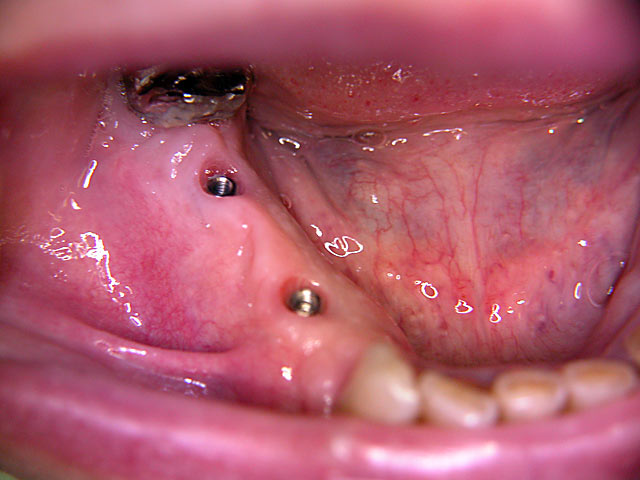

Kugelkopf-Implantation: